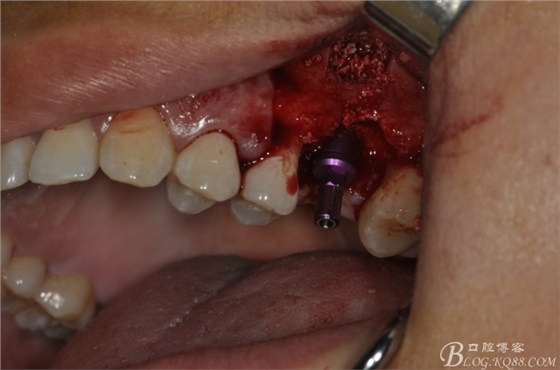

術(shù)中照片。